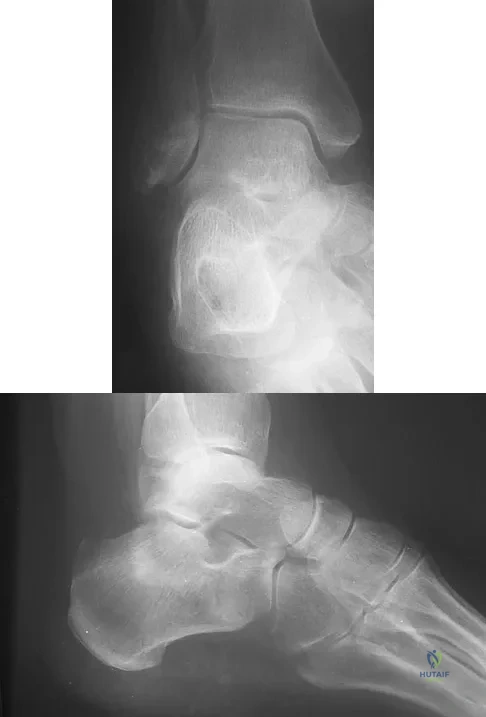

A 75-year-old woman began a walking program 2 months after undergoing right total knee arthroplasty. She had to stop the program after 4 weeks because of hindfoot pain and ankle swelling. Radiographs are shown in Figures 42a and 42b. What is the most likely diagnosis?

Explanation

A 26-year-old ballet dancer reports posterolateral ankle pain, especially with maximal plantar flexion. Examination reveals maximal tenderness just posterior to the lateral malleolus, and symptoms are heightened with forced passive plantar flexion. Radiographs are shown in Figures 42a and 42b. What is the most likely cause of the patient's symptoms?

Explanation